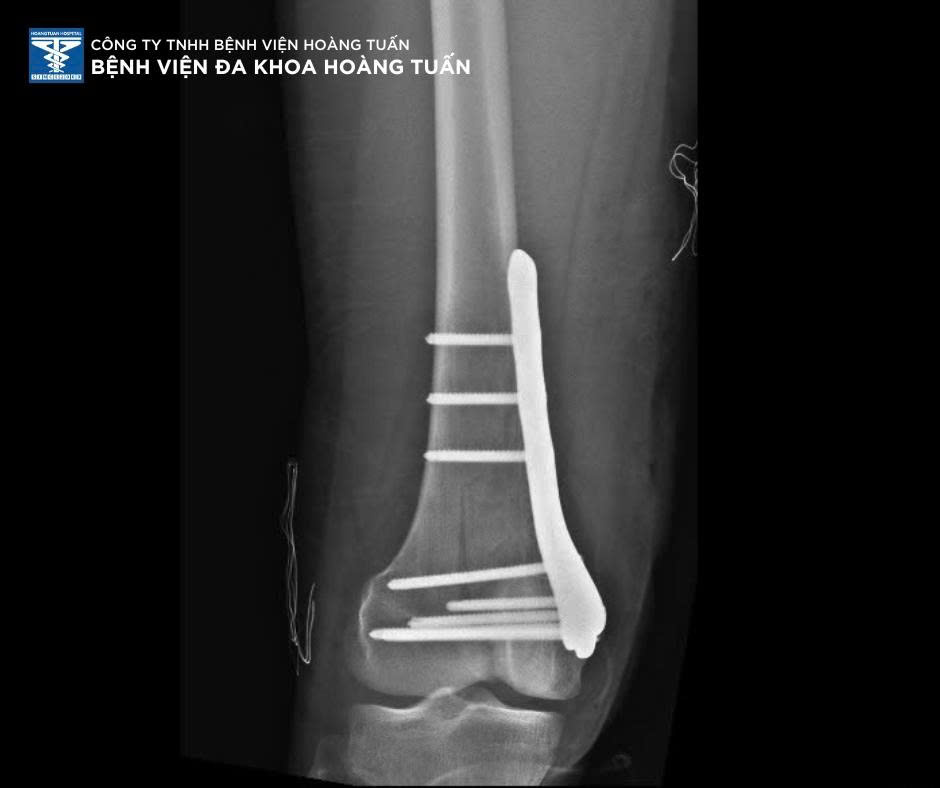

Sau 2 giờ trải qua cuộc phẫu thuật cùng BSCKI. Vũ Quốc Dũng và Ekip phẫu thuật CTCH Bệnh viện Đa khoa Hoàng Tuấn, bệnh nhân giảm sưng đau, vận động nhẹ sau phẫu thuật, phục hồi tầm vận động sớm. Với đội ngũ y bác sĩ giàu kinh nghiệm cùng hệ thống chẩn đoán hình ảnh y khoa tiên tiến, Bệnh viện Đa khoa Hoàng Tuấn luôn sẵn sàng tiếp nhận và xử trí nhanh chóng các trường hợp chấn thương phức tạp do tai nạn sinh hoạt, lao động. Quý khách có nhu cầu tư vấn vui lòng liên hệ số điện thoại bên dưới bài viết hoặc trực tiếp qua tin nhắn FB Bệnh viện Đa khoa Hoàng Tuấn.